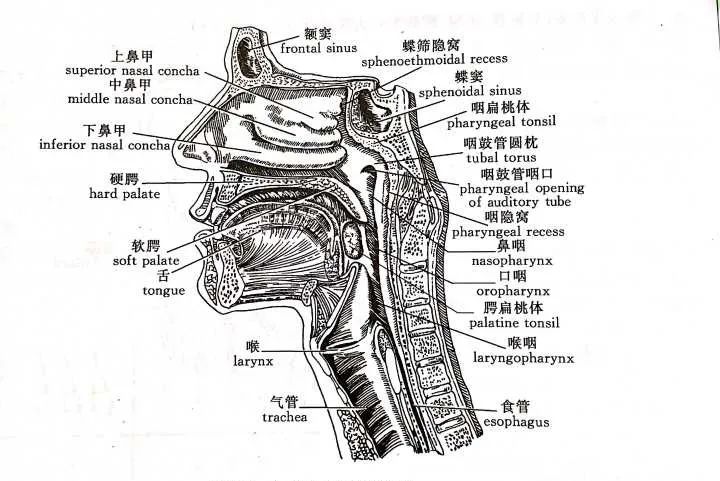

鼻咽又称上咽,位于鼻腔后方,上达颅底,下至软腭游离缘平面接口咽部,向前经鼻后孔通鼻腔;顶壁以纤维膜紧贴于蝶骨体及枕骨基底部;后壁呈垂直状,由斜坡和第 1、2 颈椎组成;侧壁左右对称,由肌肉和筋膜组成,两侧壁有凹陷的咽鼓管咽口和隆起的咽鼓管圆枕,圆枕后上方与咽后壁之间有一凹陷的咽隐窝。鼻咽顶部和后壁移行相连,呈倾斜的圆拱形,常合称顶后壁,此壁粘膜下有丰富的淋巴组织,称咽扁桃体,即腺样体。

正常成人鼻咽部粘膜较薄,表面光整、连续,粘膜下结构分界清楚,两侧壁的咽鼓管咽口、咽鼓管圆枕及咽隐窝显示清晰,在 MRI 各序列信号正常。